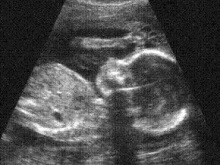

Ultrasound technology and laws credited for pro-life shift

May 19, 2009

Some doctors and pro-life leaders now say ultrasound technology is partly responsible for Americans’ gradual shift to identifying themselves as... Read more